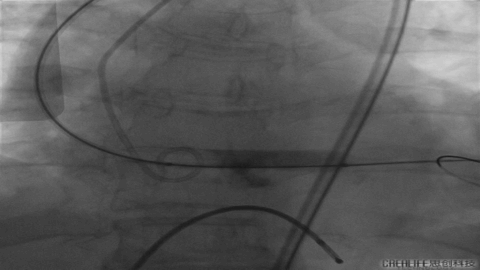

更换VenusA26号瓣膜前1/3

VenusA26号完全释放

最后一枪造影

超声显示人工瓣膜工作良好,微量瓣周漏,术后一周顺利出院,术后随访无并发症,恢复良好。